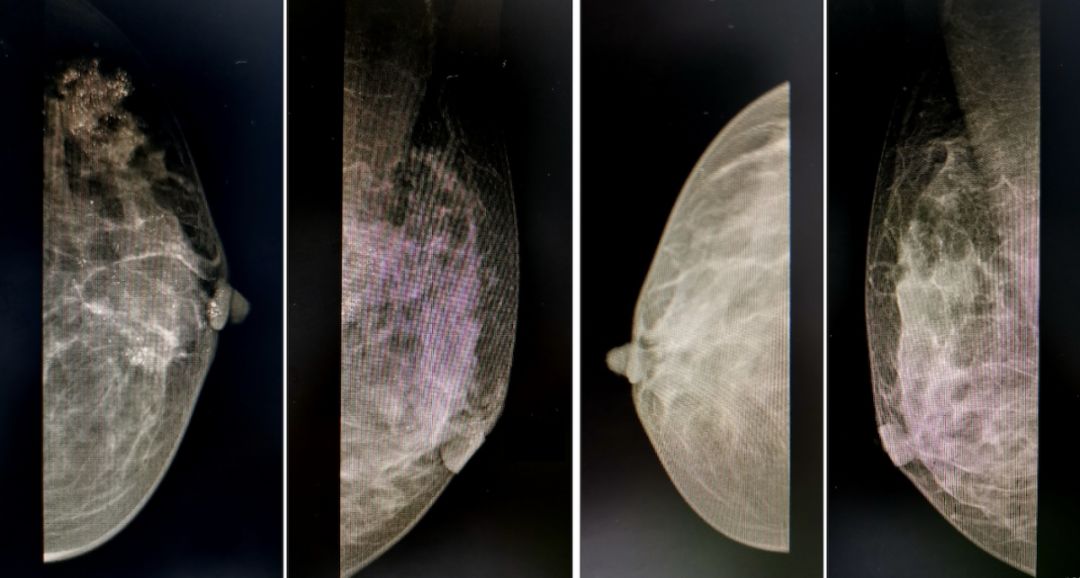

钼靶:双侧乳腺为不均匀致密类,腺体密度不均匀增浓,左乳外上可见大约为2.5 cm*2.4 cm团块状密度增浓影,其内及左后方可见大量泥沙样、不规则钙化灶,呈密集分布。乳头及周围皮肤光整,未见明显凹陷,皮下组织正常;双腋下未见明显肿大的淋巴结。钼靶诊断:左乳外上肿物,BIRADS 4a类。

图2 乳腺泪钯检查